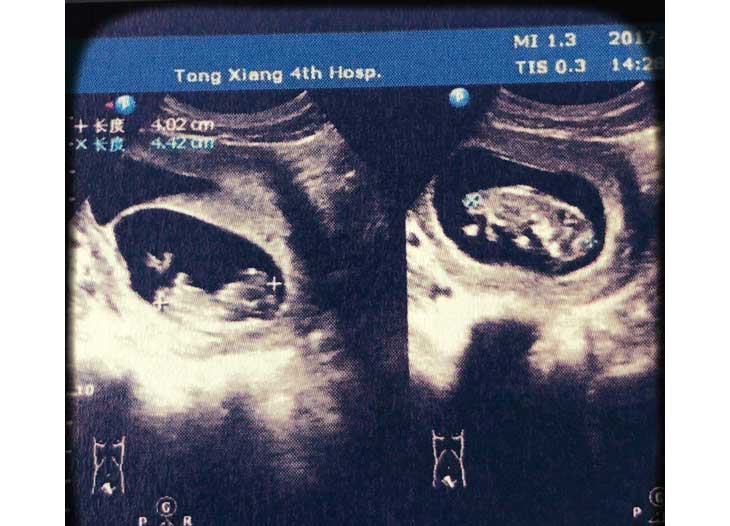

B超检查怀上双胞胎V2G育儿资讯网-育儿常识全方位解读,助您开启好孕之旅

那几天也就安心地躺在床上,小心翼翼地。一回国后大概过了14天左右,进行验血,结果血值翻倍8080,心想有可能双胎,终于熬到B超的时候,大夫也说双胞胎,都有了胎心,那一刻还是懵的,回家缓了几天,失眠了几天,突然有了前所未有的喜悦。V2G育儿资讯网-育儿常识全方位解读,助您开启好孕之旅